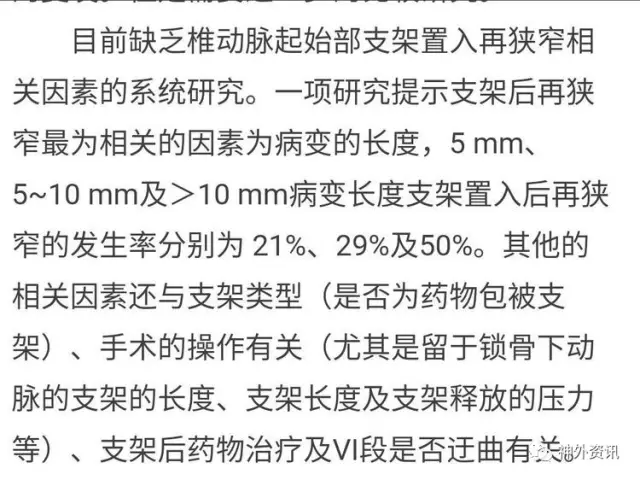

2014版VA狭窄指南:VA再狭窄目前认为主要与开口段狭窄段的长度有一定正√相关,与支架种类、扩张压力、局部开口段迂曲度有一定相关性。